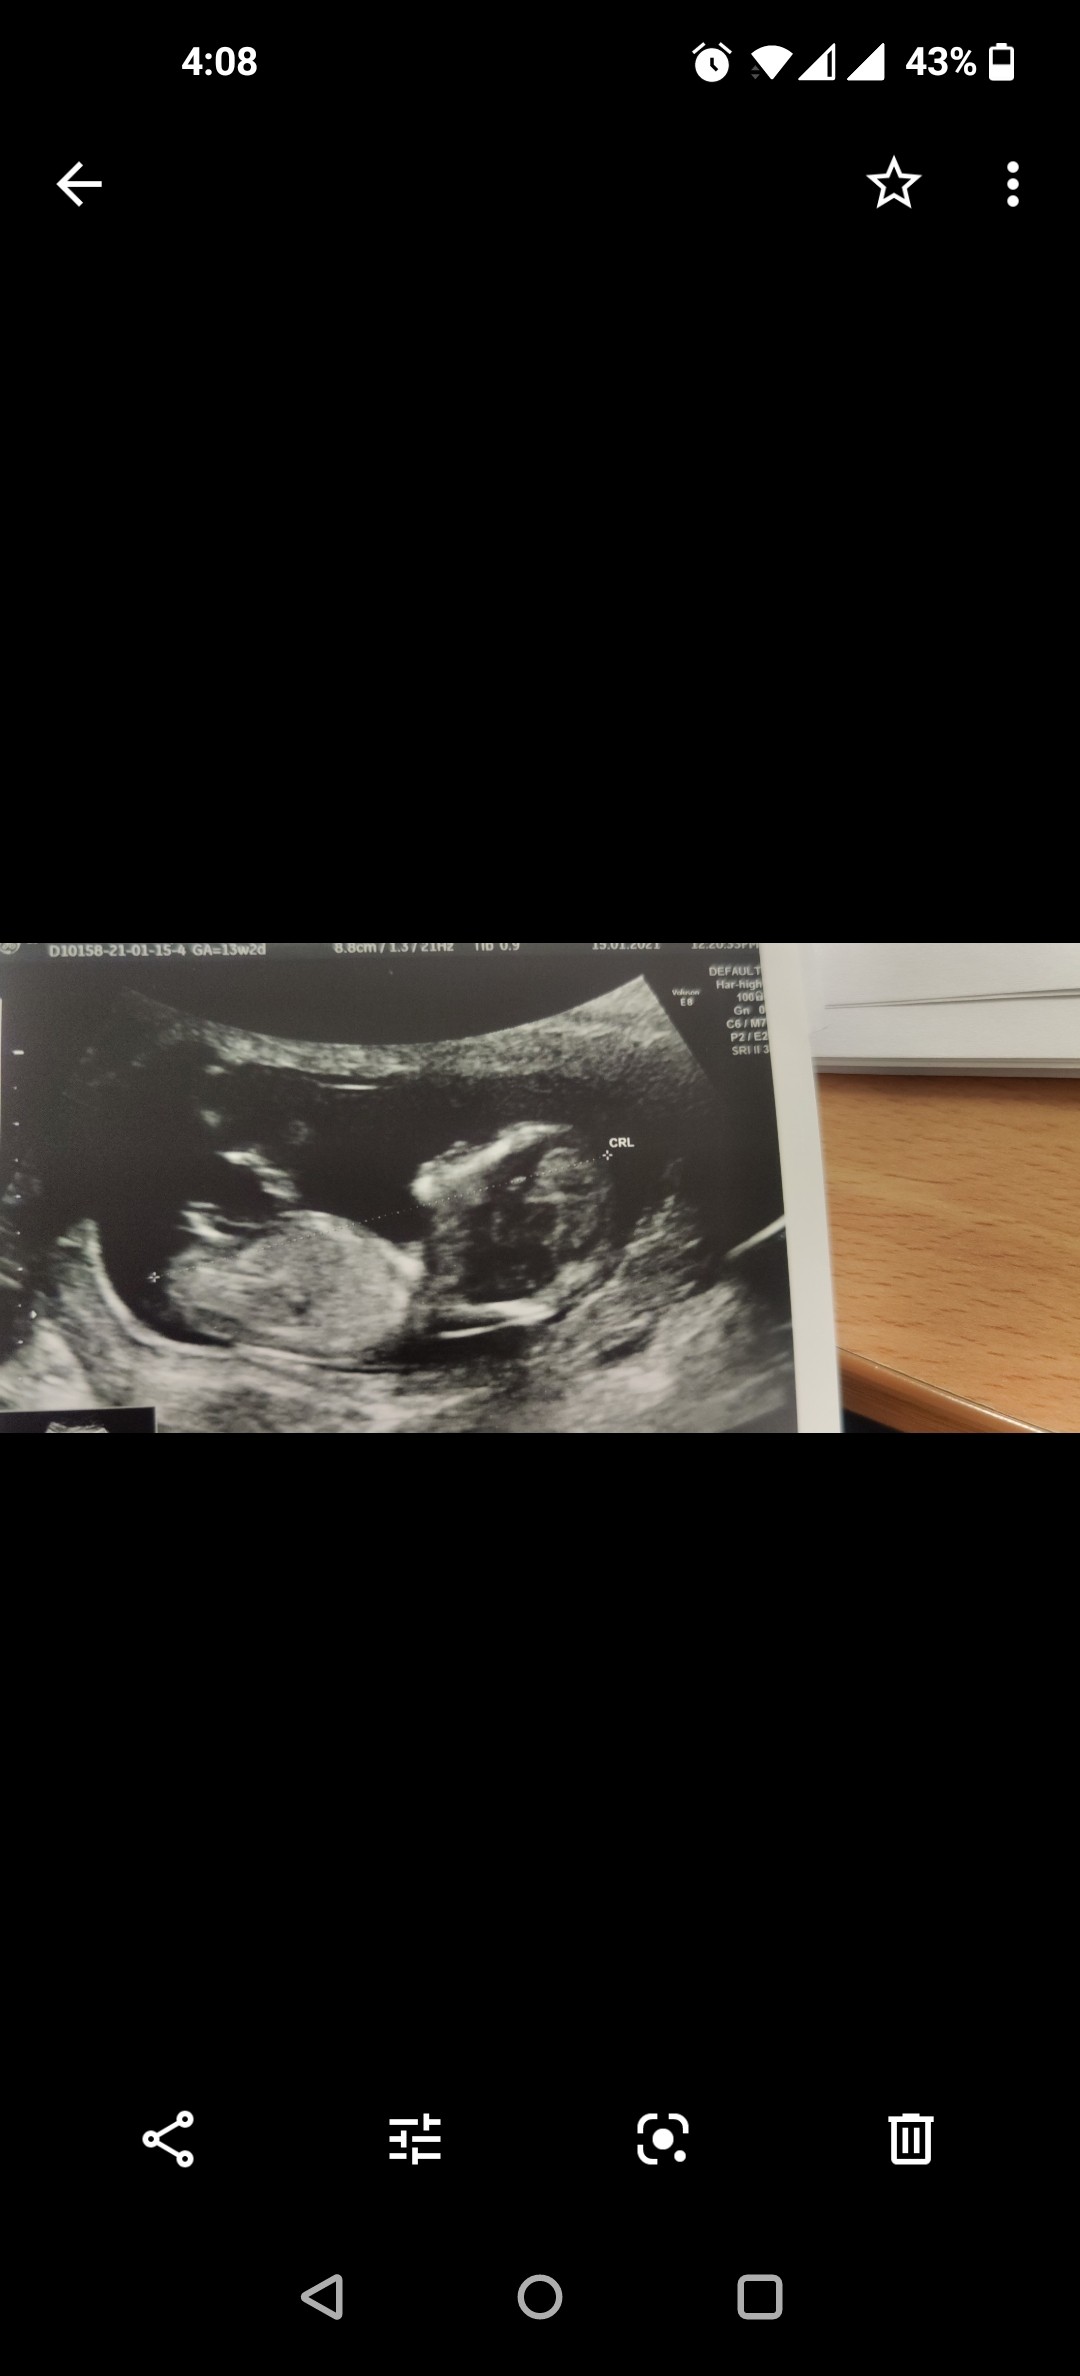

Usg chłopak czy dziewczynka

Witam w 19 tygodniu ciąży dowiedziałam się ze będę miała dziewczynkę w 20 tyg okazało się jednak , że to chłopak. Sama już nie wiem bo na jednym usg widać na pewno dziewuche a na drugim chłopca. Może to pempowina ?? Może ktoś mi pomoże rozwiązać ta zagadkę

Załączniki

• 4A8F5FF1-76CA-4DE0-AC12-5EDF08E820F2.jpg

4A8F5FF1-76CA-4DE0-AC12-5EDF08E820F2.jpg

596,4 KB · Wyświetleń: 44 138

596,4 KB · Wyświetleń: 23 778